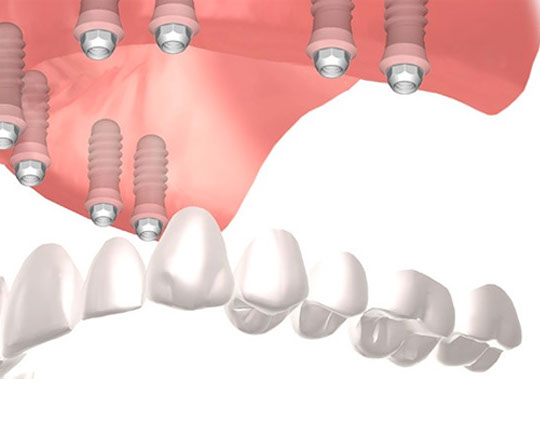

IMPLANTES

Colocamos implantes dentales que realizan la función de raíces artificiales para los dientes perdidos, proporcionando la base para un nuevo diente.

UNI: Reemplaza un diente

MULTI: Reemplaza cada pieza, similar a los dientes

PUENTE SOBRE IMPLANTE: Cuando faltan varias piezas, no hace falta un implante por cada diente.

PRÓTESIS HÍBRIDA: Falta la totalidad de los dientes, y devuelve función y estética.